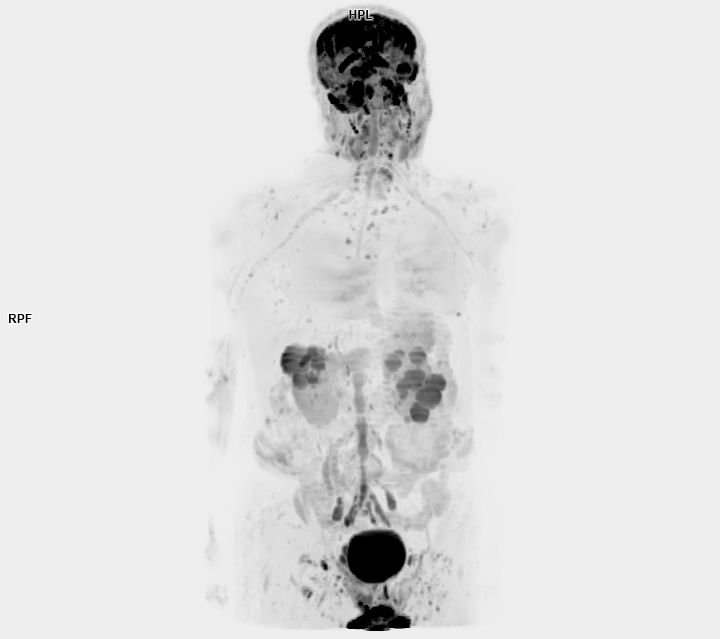

• 3 TESLA MR ÇEKİM GÖRÜNTÜLERİ

3 Tesla MR Çekim Görüntüleri

• 3 Tesla MR Çekim Görüntüleri